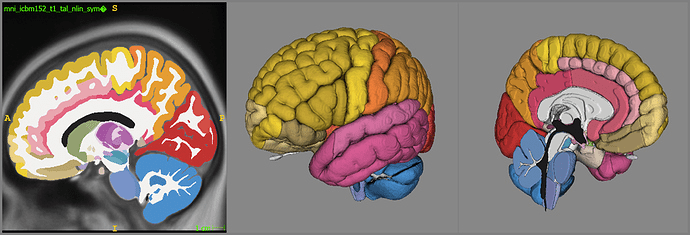

Can we segment one human brain and then apply this output to many human brains?

Can this label map be applied to many different scans?

Yes!

Atlas-based Segmentation

Registration / Alignment

Registration

mapping one subject to a standard space

mapping one image modality to a standard space

once in standard space, we can apply knowledge or compare